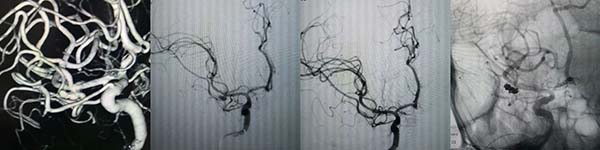

病例1:“密网支架”辅助弹簧圈栓塞血泡样动脉瘤

70岁的孟先生突发蛛网膜下腔出血,脑血管造影显示左侧颈内动脉眼动脉段血泡样动脉瘤,团队采用“血流导向装置”(密网支架)置入,通过改变血流方向,并填塞一枚弹簧圈,降低动脉瘤复发率。

病例2:三微导管技术,支架辅助弹簧圈栓塞宽颈分叶状动脉瘤

韩女士诊断为左侧颈内动脉眼动脉段破裂宽颈分叶状动脉瘤,团队采用“三微导管”技术,动脉瘤内放置两根微导管,交替分区填塞弹簧圈,第三根微导管放置于载瘤动脉内用于释放支架,实现致密栓塞。